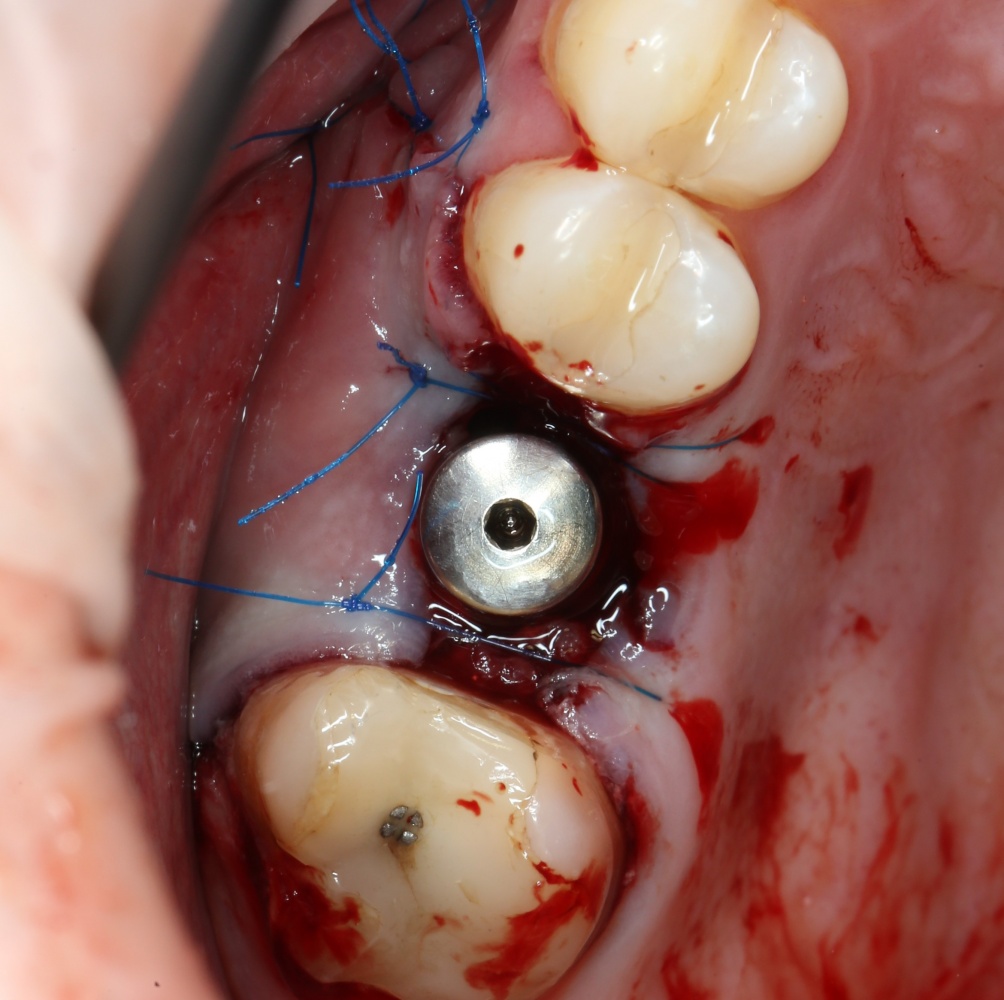

Устанавливается имплантат Astratech (Dentsply Implants):

Для аугментации также используем Bio-Oss Collagen 100 mg, нарезаем его по размеру с помощью скальпеля и позиционируем в лунках щечных корней:

На имплантат ставим формирователь, ушиваем лунку. Напомню, что любой биоматериал должен быть герметично запечатан в ране (фактор успеха III). В противном случае, от него больше вреда, чем пользы:

Совсем уж стягивать края раны не нужно (если бы мы использовали обычный Bio-Oss, то это было бы необходимо). Отличие Bio-Oss Collagen еще и в том, что он не размывается при кровотечении.